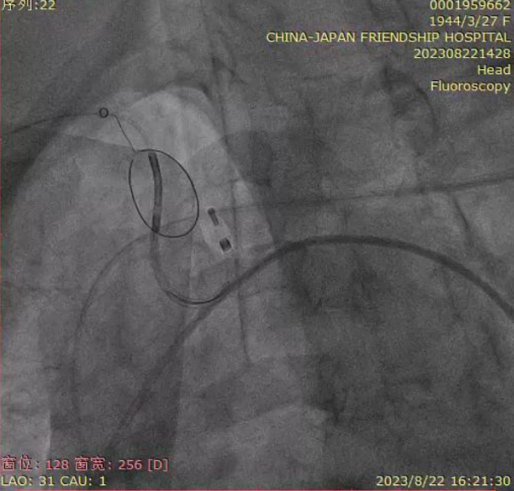

TaurusEliteAV23第二次定位、释放;

零位释放,瓣膜位置过高,回收并进行第三次释放。第三次释放后,多体位根部造影评估,瓣架底边对齐,左冠显影良好,瓣膜明显位移,同轴性较差,瓣膜压缩,决定第三次回收;

第四次定位和释放,右窦中心位,瓣上2mm释放;

根部造影评估,瓣架底边对齐,左冠显影良好,同轴性一般,瓣膜压缩,锚定良好,瓣下深度4-5mm;